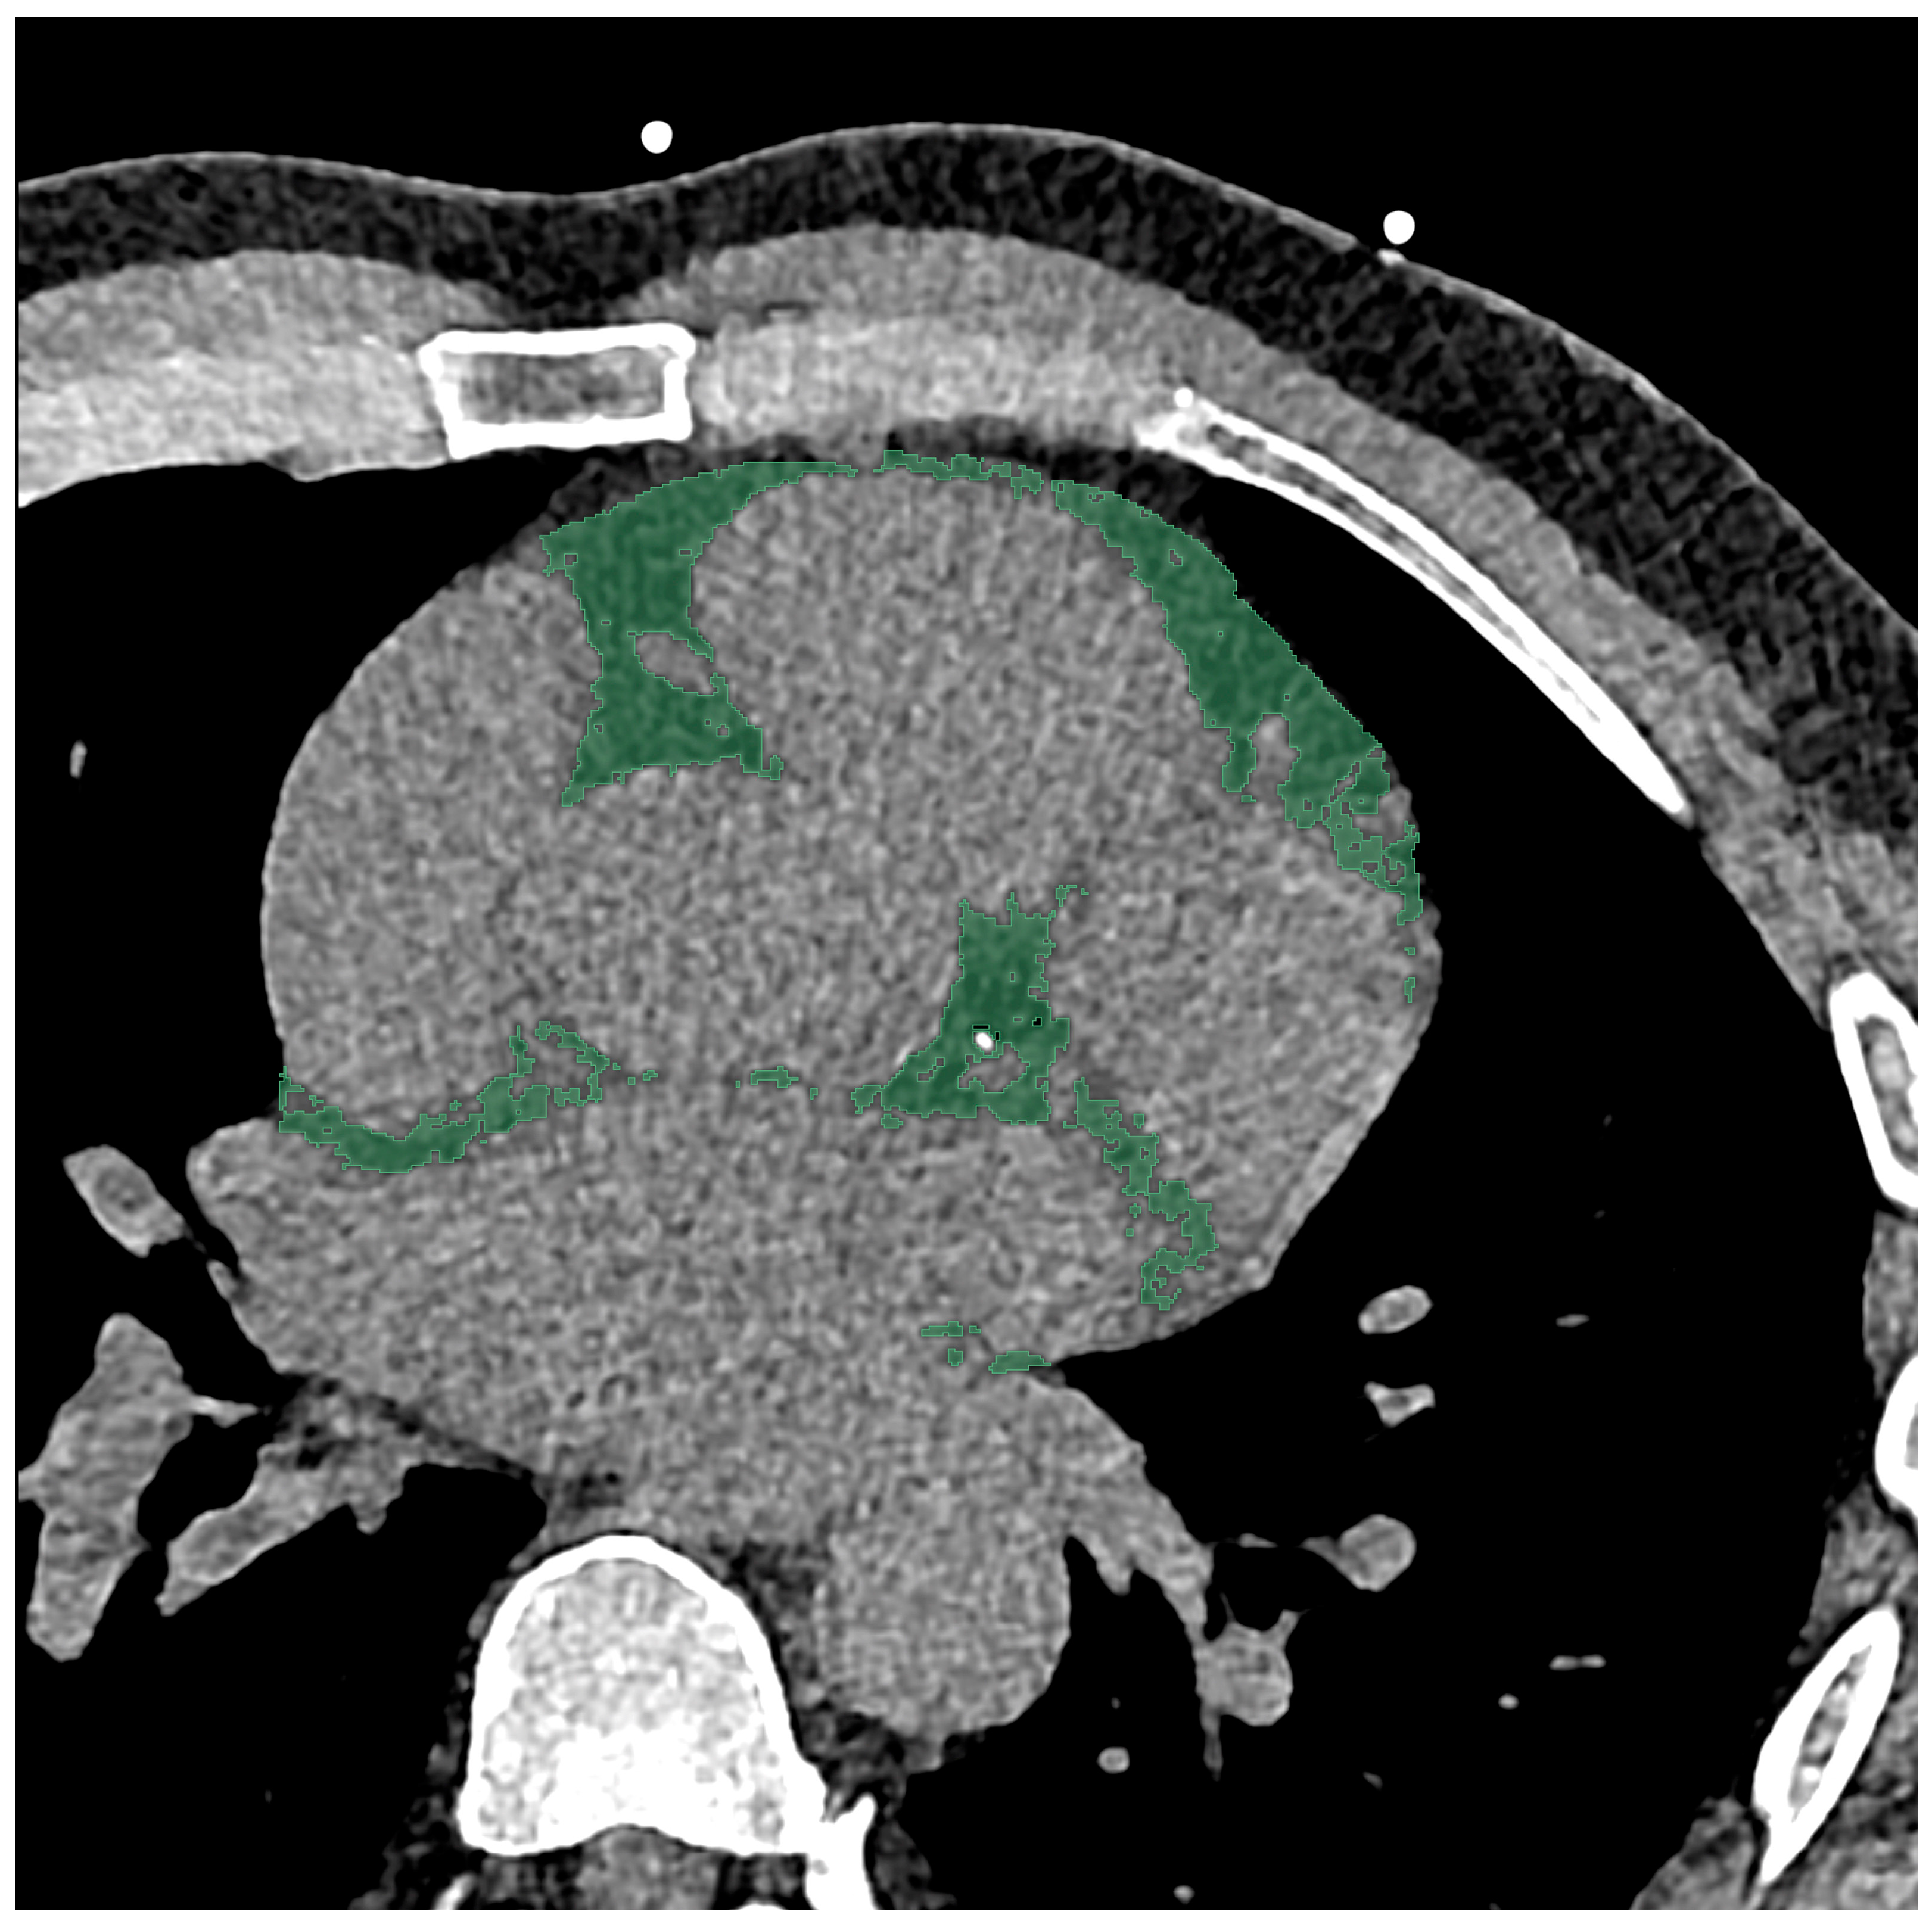

2.3. Chest CT Imaging Analysis